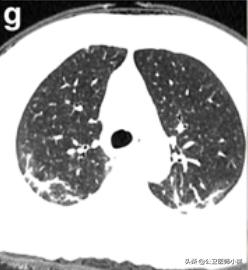

肺部感染涉及多个肺叶-1

肺部感染涉及多个肺叶-2

肺部感染涉及多个肺叶-3

根据感染的不同程度累积一个或多个肺叶